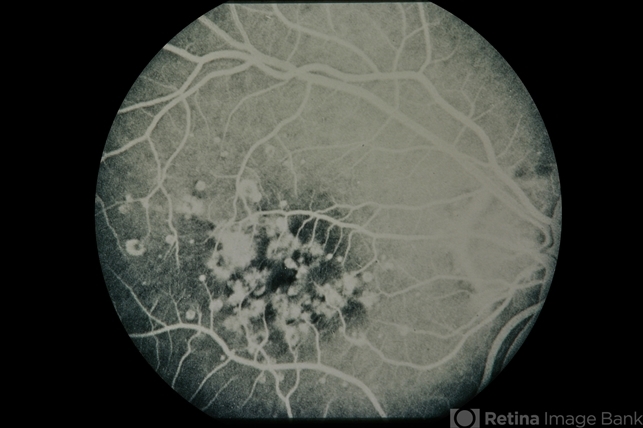

- Grouped Albinotic Spots in Macula

- Condition/keywords

- albinism, macula

- 39-year-old female, 20/15 OU; normal color, ERG, EOG, thresholds, VF.